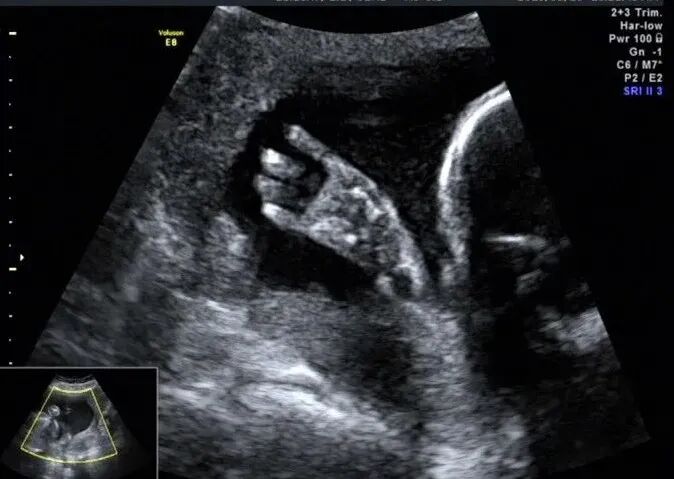

再看脚也不对劲,马上启动三维超声,下图是三维超声表现

手脚都有问题,呈龙虾爪样,非常典型的手裂足裂,胎儿父母没有啥疾病